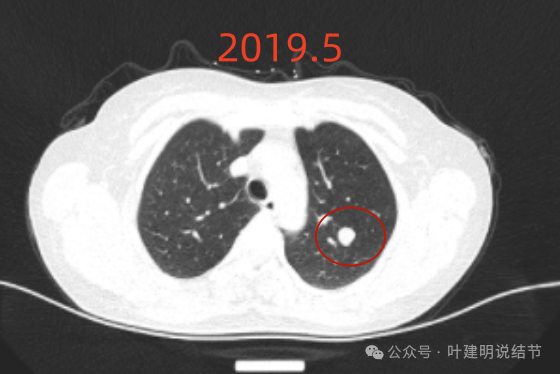

先看不同时间段的病灶影像:

2019年5月时左上叶实性结节,边缘很光滑,没有毛刺或血管征,影像上看像良性的。